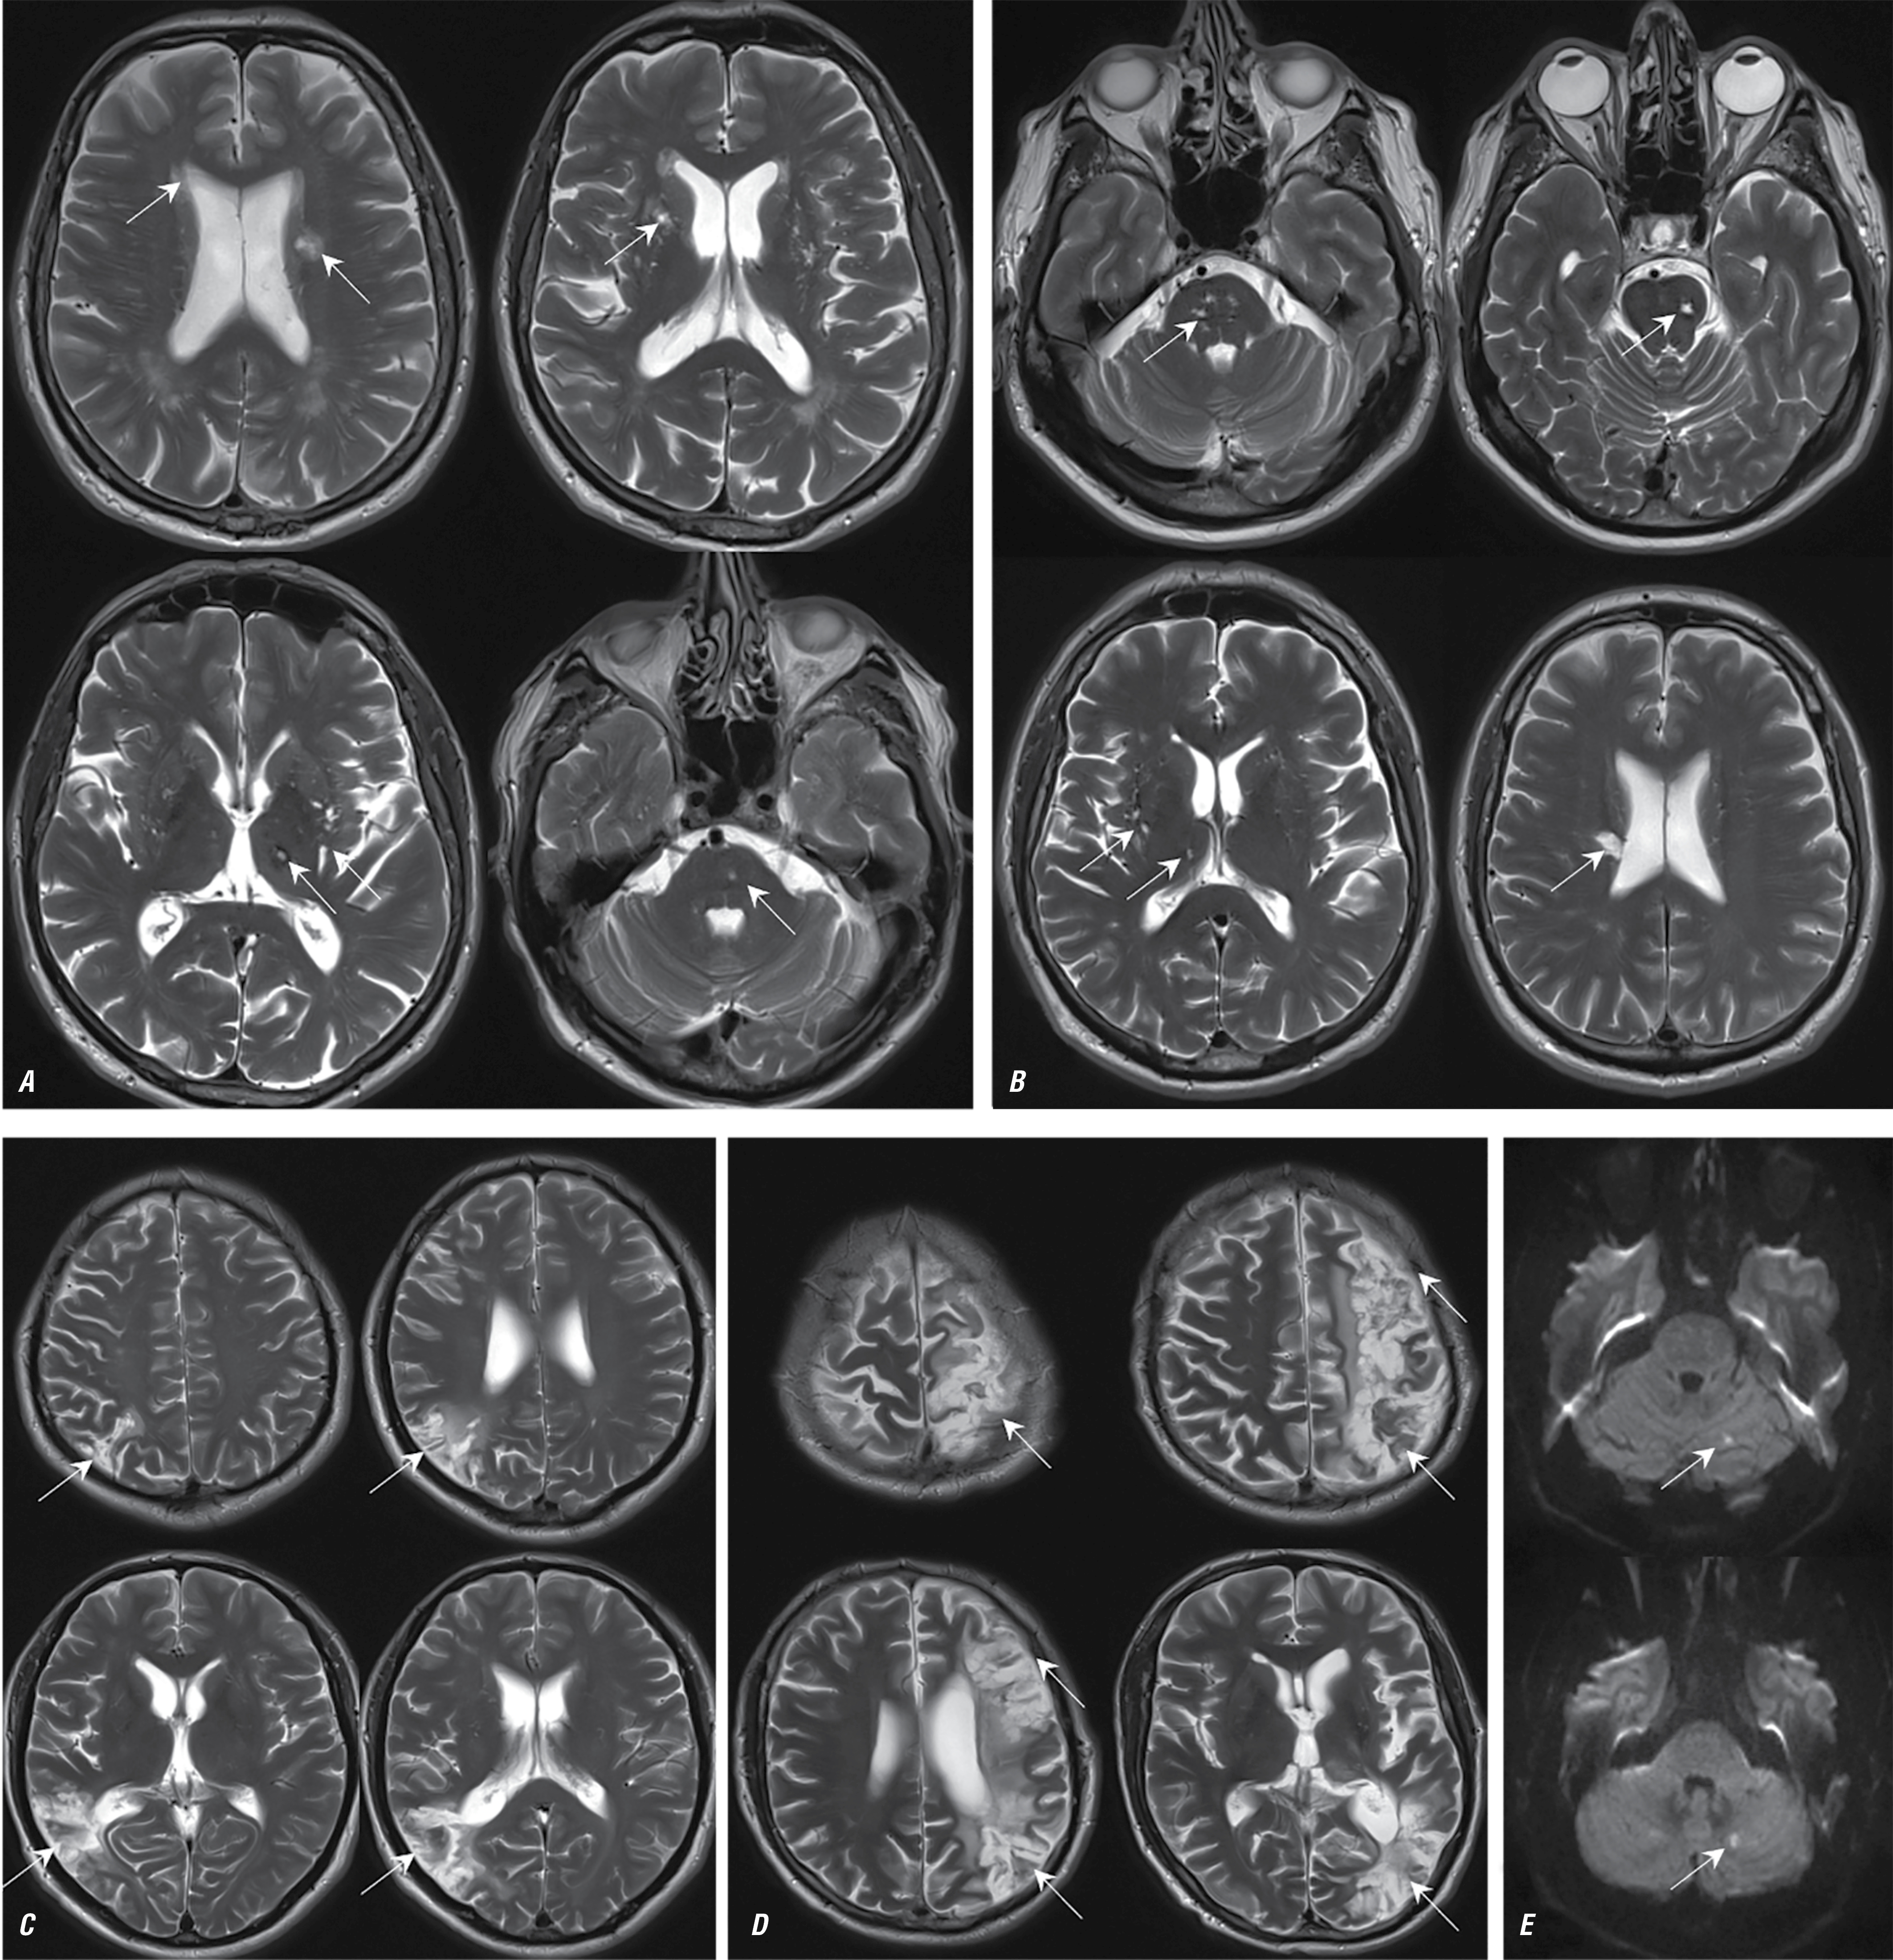

Рис. 5. МРТ головного мозга пациентов с ПМФ в аксиальной проекции в режиме Т2 (А, С) и в сагиттальной проекции в режиме Т2-FLAIR (B, D).

Визуализируются небольшие постинфарктные перивентрикулярные очаги (указаны стрелками).

Fig. 5. Brain MRI of patients with PMF in axial T2 images (А, С) and in sagittal T2 FLAIR images (B, D).

Small post-infarction periventricular lesions are visualized (as indicated by arrows).

Первичный миелофиброз

Характерными клиническими признаками НМК на фоне ПМФ у большинства обследованных являлись рецидивирующие преходящее онемение в руках/ногах, неловкость при выполнении мелких движений, самостоятельно купировавшиеся в течение нескольких часов по типу транзиторной ишемической атаки. Часть пациентов описывала эпизоды транзиторной ишемической атаки в течение нескольких недель, месяцев до развития НМК. Несколько пациентов отмечали приступы выраженной, атипичной головной боли с появлением ауры (в виде «ряби» перед глазами, изменения цветоощущения), с последующим развитием очаговых изменений (в течение нескольких недель).

Средний возраст пациентов с инсультом на фоне ПМФ составлял 50 лет, ни в одном случае постинфарктные изменения не приводили к стойкой утрате трудоспособности с выраженным двигательным дефицитом.

Основным паттерном постинфарктных изменений у пациентов с ПМФ при нейровизуализации являлись небольшие очаговые поражения в глубоких отделах вещества мозга, вероятнее всего, после развития НМК по типу гемореологической микрооклюзии (рис. 5).